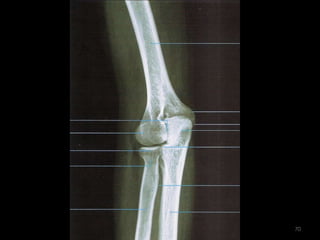

Incidência AP de cotovelo62

63

64

Incidência lateral cotovelo (látero-medial)65

66

67